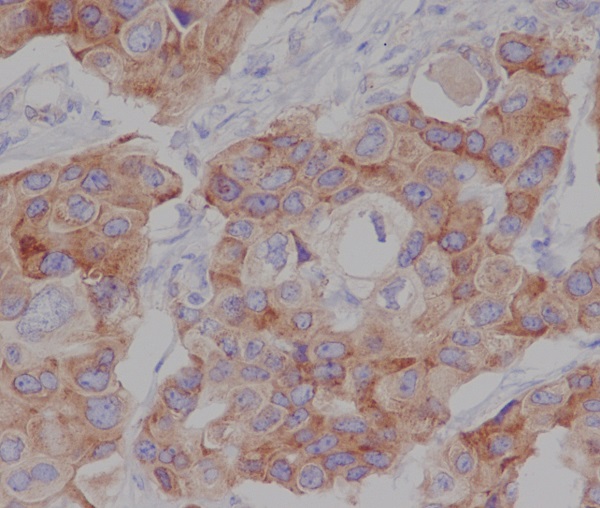

Immunohistochemistry analysis of paraffin-embedded human breast cancer using Phospho-mTOR (S2448) antibody. High-pressure and temperature Sodium Citrate pH 6.0 was used for antigen retrieval.